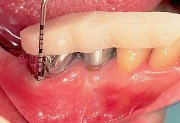

5

| 添付されている吸収性の縫合糸を用い、歯面と緊密に接する様に注意しながら歯牙へ固定してゆく。メンブレン固定後はプローブ等を用いて歯面との間に上皮が入るスペースがないことを確認しておく。 |

6

| 歯肉弁を縫合する前に、頬側に減張切開を加え、メンブレンをテンションが加わることなく覆えることを確認し、メンブレンに近い歯肉より縫合をすすめていく。 |